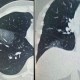

新冠病毒感染的症状范围较广,从无症状感染到重症肺炎均有,目前主流毒株(如奥密克戎系列)引起的症状以下列为主: